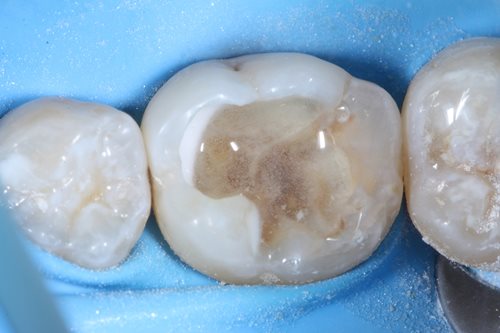

Since the infected bottom left molar already contained a filling, Dr. Benjamin removed the old filling material with the help of a diamond bur. After this, he removed the secondary caries by using an EndoTracer, but then switched to a hand instrument to precisely clean the remaining tooth substance.

After complete removal of the secondary caries, a partial pulpotomy of the infected but still viable dental nerve was carried out by creating an access cavity with a bur in order to gain access to the mesial pulp horn. To open the mesial pulp horn, Dr. Benjamin used a new sterile instrument to minimize the risks of infection. This was followed by a millimeter accurate excision of the pulp horn, making sure that the pulp horn is removed evenly to create a levelled surface area for the Komet BioRepair putty filling material that is applied later.